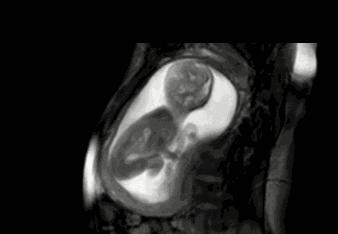

在孕妈的一整个孕期都有很多需要注意的地方,尤其是随着胎儿的逐渐长大,不可能每天都去医院检查胎宝是否健康,此时数胎动就成为孕妈观察胎宝健康状况的一个重要举动。只是,作为新手孕妈,你真的会数胎动吗?

有些孕妈比较心急,从20周,甚至16周就开始数胎动,其实这个月份数下来并不是很准。因为在这个阶段,孩子的胎动并不是很明显,频率也比较低。一般建议是在28周,也就是胎儿七个月的时候,孕妈开始数胎动。这个时间段的胎动最为活跃,孕妈也最需要注意胎儿的健康。

胎儿的胎动和孕妇的体位也有着密切的关系,数胎动最好的姿势是,左卧。因为在站立、右卧或者平躺的时候,胎儿的胎动次数相对较少。